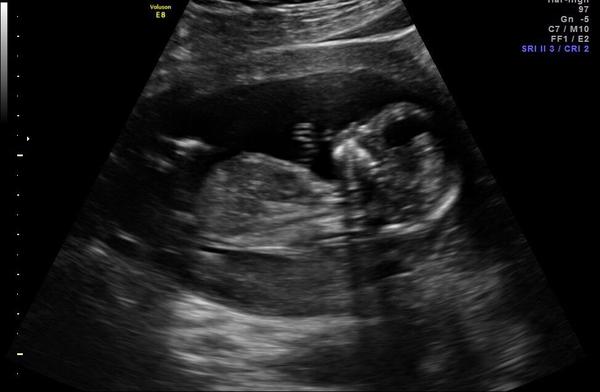

Holka nebo kluk? Poznáte z fotky?

Ahoj holky, na konci července jsem byla na prvním screeningu a nezeptala jsem se na pohlaví, doktorka taky nic nezmínila. Ale pořád prohlížím fotku a snažím se z toho zjistit, co by to mohlo být, ale nic z toho nepoznám 😀 jsem hrozně zvědavá a na další utz jdu až v září. Prosím tipnete si, jestli něco vidíte.

@elsy3 mimco mas z profilu, to asi nic neuvidis. Na 1.screeningu pohlavi pozna jen maloktery dr.natoz my tady 😅 kolem 16tt by Ti dr.mohl tohle tajemstvi prozradit, pokud se malicke rozhodne spolupracovat, kdyz tak ve 20tt+ velky utz. Uz se na nej tesim, snad nam na nem za 3 tydny reknou, co cekame.

Z takovehle fotky to snad ani nejde poznat. Neni tam videt to nejdulezitejsi-ta cast panve a zadku s nozkama. To se pak da pry poznat dle smeru pohlavniho hrbolku,ale na 1.screeningu si vetsinou netroufaji rict.